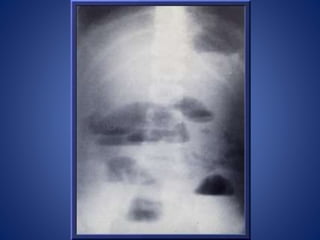

RADIOLOGICAL EXAMINATION

Gas fluid levels are the most important criteria

of diagnosis of intestinal obstruction.

When obstruction occurs, both fluid and gas

collect in the intestine.

They produce a characteristic pattern called

"air-fluid levels". The air rises above the fluid

and there is a flat surface at the "air-fluid"

interface.